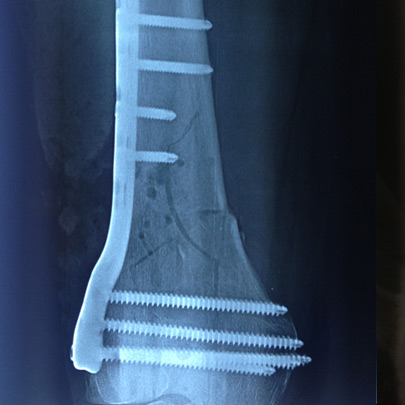

Fracturas y luxaciones

Tratamientos quirúrgicos

Cirugía de tobillo